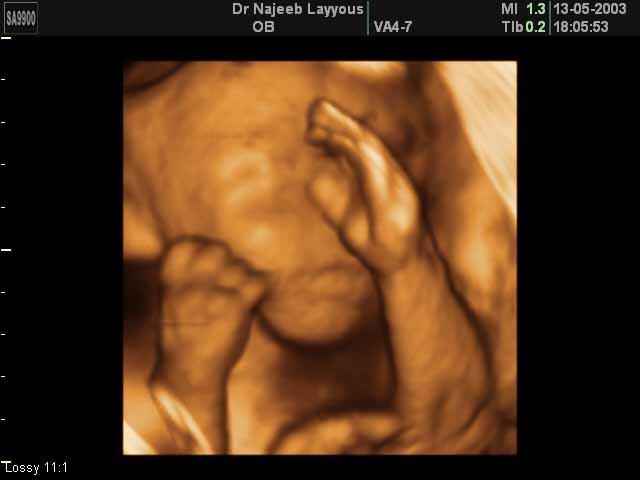

- تصرفات الجنين داخل الرحم

- صور لأعضاء الجنين

- صور لأطراف الجنين

- صور لتصرفات الجنين داخل الرحم